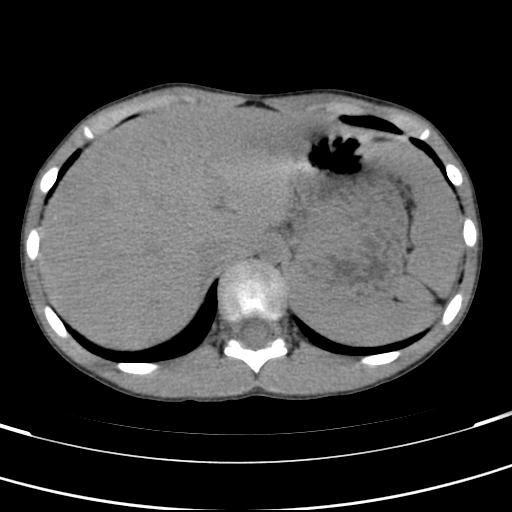

标题: PED3157:左肾缺如,请教脾脏的改变?、、

男孩,9岁。胃部不适。

脾脏变异,左肾未见,游走、异位、发育不全都要可能,增强或ivp造影。

脾脏位于左侧,但数个脾脏呈分离状态,左肾缺如,右肾代偿肥大。考虑多脾综合征。

同意三楼意见,符合多脾综合症。